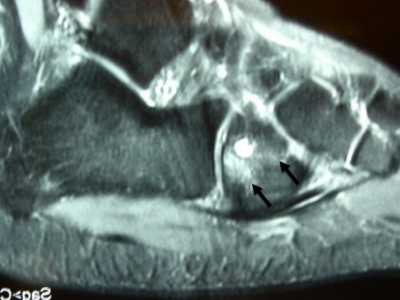

Exemple de fracture de fatigue du cuboïde droit:

Parfois on peut voir le trait de fracture sous la forme d’une ligne noire (hyposignal).

Cet examen permet d’éliminer les autres causes de douleurs pouvant survenir en l’absence de traumatisme (tendinites).

Cet examen qui étudie tous les tissus de la région concernée, met en évidence une zone d’hypersignal osseux qui correspond à une zone d’inflammation.